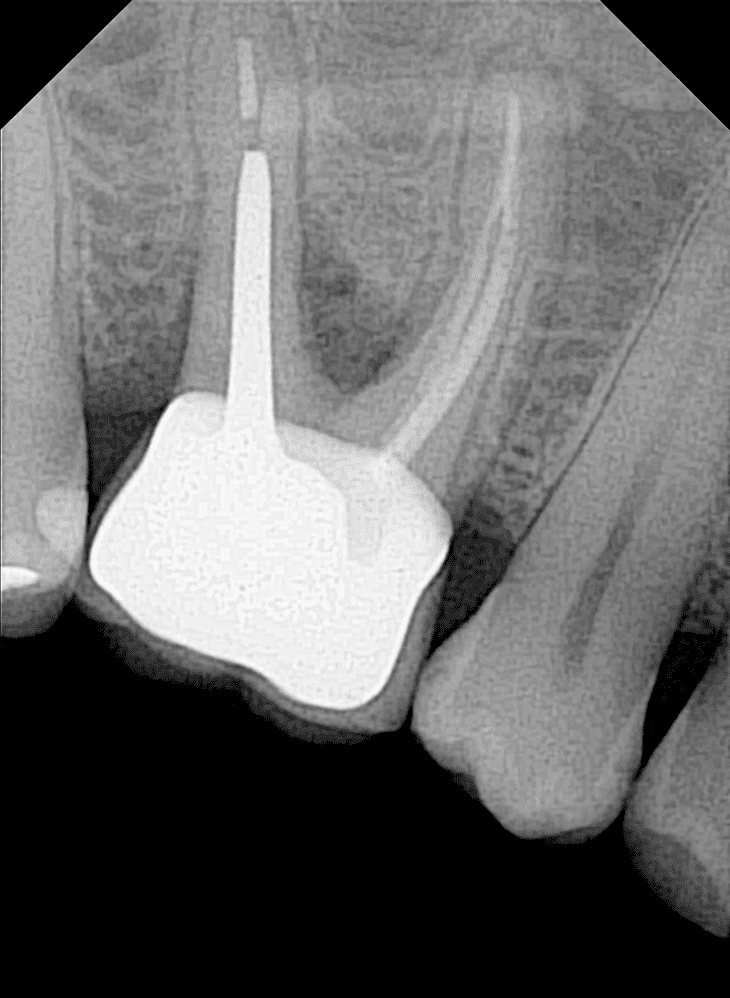

OPTEO Sensor – Klinische Bildgalerie

Ultra-HD Bildqualität – 18,5 Mikron Präzision Außergewöhnlich klare und detaillierte intraorale Bildgebung.

- Endodontie: Verbesserte Präzision für erfolgreiche Wurzelkanalbehandlungen.

- Kariesdiagnostik: Präzise Erkennung selbst frühzeitiger Läsionen.